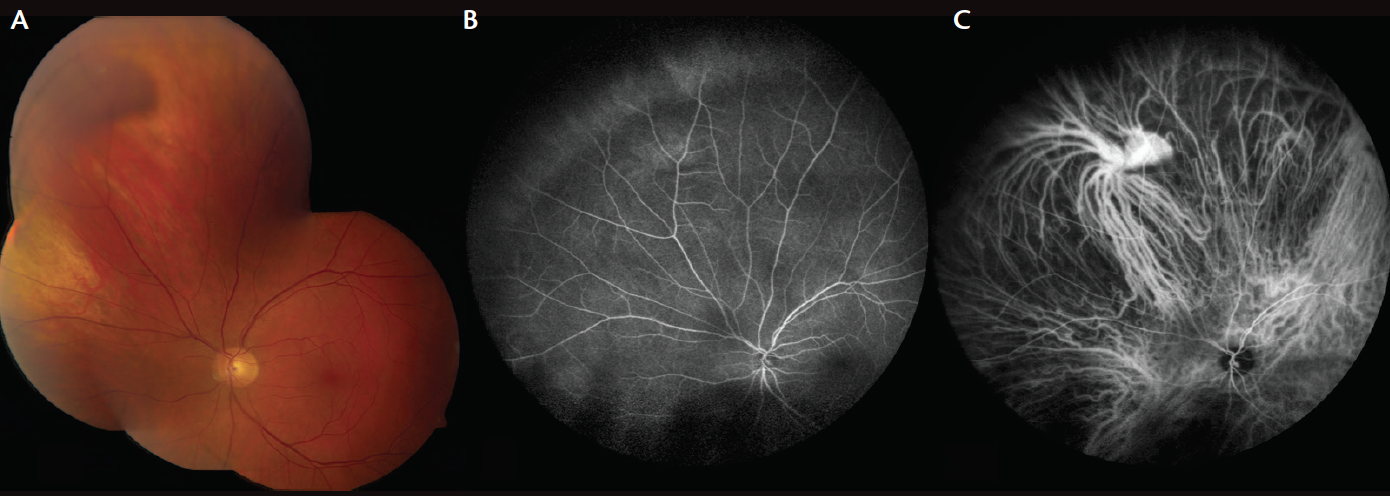

On examination, the patient’s BCVA was 20/20 in each eye (OU), and intraocular pressures were normal at 12 mm Hg OU. His right eye was otherwise unremarkable. Evaluation of the left eye revealed a healthy anterior segment and intact macula. Upon gaze superonasally, a red-brown dome-shaped mass was visible, measuring 3 mm in basal diameter and 2 mm in thickness, located at the globe equator and without subretinal fluid or orange lipofuscin pigment (Figure 1A). At the time of examination, it was noted that the mass fluctuated, with deflation in primary gaze and reinflation when the patient’s gaze was along the meridian of the mass, suggestive of VVV and not melanoma.

Figure 1. A 55-year-old man was referred with pigmented choroidal melanoma. Fundus image of the patient’s left eye revealed a red-brown lesion superonasally (A). Fluorescein angiography showed minimal hyperfluorescence superonasally corresponding with area of lesion (B). ICGA demonstrated good choroidal flow and a clear outline of the dilated vortex vein ampulla corresponding to the mass (C).

Imaging with ultrasonography demonstrated a small choroidal mass. Its thickness of 2.0 mm was reduced to 1.1 mm with digital pressure on the globe. Fluorescein angiography showed a slight blush of choroidal hyperfluorescence at the site during varix inflation (Figure 1B). ICGA documented delineation of the hypercyanescent vortex vein ampulla with slow filling of the dilated ampulla taking more than 44 seconds (Figure 1C). The ampulla had approximately 17 tributaries feeding into it. At maximum dilation, the varix measured 2 mm in diameter. Upon digital pressure to the globe, the varix deflated slowly over 1 minute to a diameter of 1 mm.